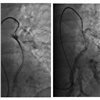

В больнице рассказывают, что одним из первых пациентов, на котором опробовали метод механической фрагментации тромба, стала 18-летняя девушка. В тот день утром ее выписали из другого стационара после операции на сломанном бедре, а вечером ее доставили в сосудистый центр больницы № 20 в тяжелом состоянии с симптомами тромбоэмболии. Врач-реаниматолог Владимир Радионов предложил попробовать разрушить тромб, который то перекрывал ток крови полностью, то частично открывал артерию. Для этого в легочную артерию под рентген-контролем ввели катетер, который обычно используется для оценки гемодинамики в отделах сердца. Девушка открыла глаза и стабилизировалась прямо на операционном столе и в скором времени была выписана из стационара со значительным улучшением.

Применяемая в 20-й больнице методика позволяет врачам через один прокол проникнуть в венозную сеть, откуда через сердце добраться до легочной артерии и ее ветви. Тромб разрушается на фрагменты. Это позволяет быстрее его растворить и избежать тяжелых осложнений за счет сокращения времени и снижения количества препарата. Врач наблюдает за процессом с помощью ангиографа. Для этого пациенту в кровь вводят контрастное вещество.

«Такая операция длится от получаса до двух часов, зависит от сложности доступа к тромбу, количества изгибов сосудистого русла, по которым нужно пройти, объема действий, которые нужно выполнить врачу-оператору. Есть тромбы очень податливые, которые буквально разрушаются на глазах. Есть такие, с которыми приходится изрядно повозиться. Как только удается разрушить тромб, в область тромбоза или непосредственно в тромбомассы вводится тромболитик, который завершает процесс» рассказали в минздраве.